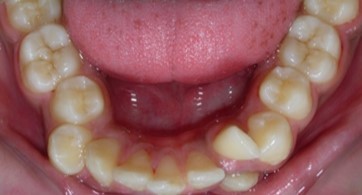

Intraoral assessment. (Figure 1d,Figure 1e,Figure 1f,Figure 1g,Figure 1h).

Figure 1h.Pre-treatment intra-oral-Lower occlusal

Pre-treatment intra-oral-Lower occlusal

The maxillary arch was V-shaped with severely proclined and rotated maxillary incisors with a palatally placed 12. The mandibular arch was U-shaped with severe crowding of mandibular incisors, with 43 partially erupted and buccally placed with transpositioned 42 and 43, with 42 mesiolingually rotated, 33 distolingually rotated and 34 distolingually rotated and buccally placed.

Severe increase in overjet and deep bite were both observed. The maxillary midline coincided with the skeletal midline but the mandibular midline was shifted to the right side by 1 mm. Bilateral maxillary posterior crossbite was also observed. On right side the molar relation was Class I and on the left side it was Class II. The canine relation was Class II on the left side and the curve of Spee was increased.